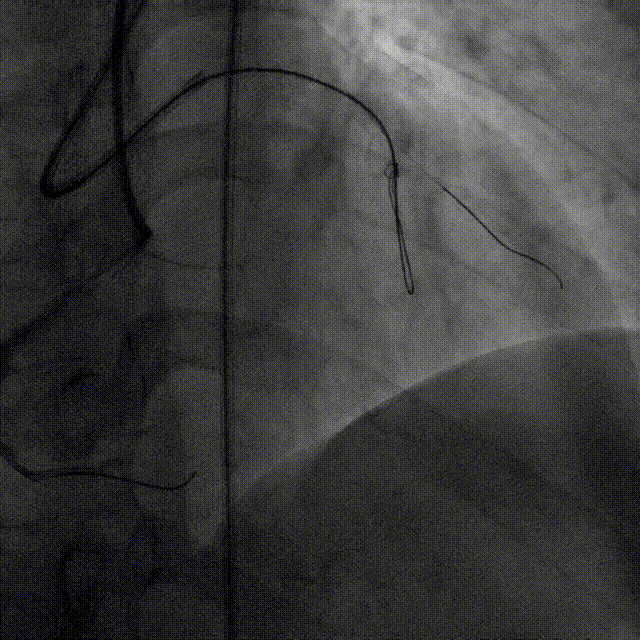

逆向导丝送至LAD近端,沿正向导丝送入2.0mm球囊扩张,在HighTrack微导管支撑下应用Gaia Third、Conquest pro 12导丝尝试Reverse CART成功

Reverse CART技术

Reverse CART是于2000年代中期,由日本介入治疗专家Osamu Katoh改进CART技术发展而来,其主要原理是正向送入导丝和球囊,在CTO病变处扩张,继而操控逆向导丝通过前向球囊产生的通道最终进入CTO近端的血管真腔。若闭塞段长度较长、迂曲、预期闭塞段内解剖结构复杂且其他CTO介入技术成功率较低,建议尽早行R-CART